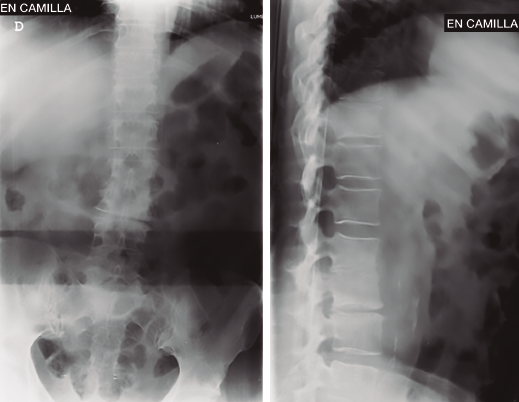

Figura 2. Resonancia magnética inicial realizada en el hospital de origen. Imagen de discopatía muy evolucionada con posible hernia L2/L3. Sagitales T2.

Se realizó analítica completa: hemograma normal, marcadores proteína C reactiva (PCR) y velocidad de sedimentación globular (VSG) claramente elevados, 80 y 63 respectivamente, Rx y RM (Figuras 1 a 4).

Figura 4. Resonancia magnética al ingreso en nuestra unidad. Secuencias T1 y T2 sagitales y axiales. Destrucción discal, edema masivo en disco y vértebras adyacentes, y colecciones líquidas anteriores y posteriores, disecando incluso psoas iliaco.